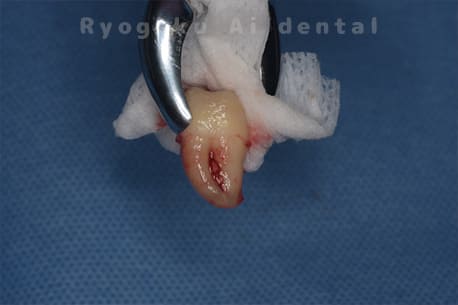

Case27

-

重度カリエス

歯牙移植咬合面術前 -

移植する親知らず

歯牙移植術直後咬合面

歯牙移植術後咬合面

歯牙移植術前側面

歯牙移植術中側面

歯牙移植術後側面

- 原因

- 重度カリエス

- 治療内容

- 自家歯牙移植、部分矯正

- 治療費用

- 220,000円(移植費用)

110,000円(部分矯正費用)

虫歯が大きく、保存不可能となった歯を上の親知らずと交換する自家歯牙移植を行いました。移植歯が小ぶりであったため、部分矯正を行い問題なく噛み合い、経過良好です。